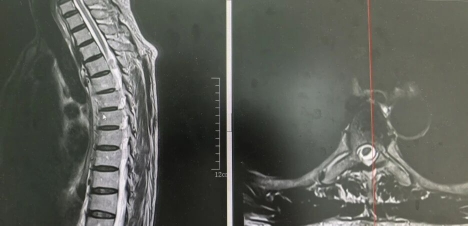

“再拖下去可能站不起来了!” 在家人的劝说下,李大爷来到西安高新医院检查。影像学结果显示,他的胸四椎体后缘水平椎管内存在一个占位性病变 —— 一颗大小类似鹌鹑蛋的肿瘤。更危险的是,这颗肿瘤已占据椎管容积超 70%,对脊髓形成严重压迫,且与保护脊髓的硬脊膜粘连紧密,分离难度极大。此外,李大爷还有 15 年糖尿病史,血糖控制不稳定,这无疑给手术风险和术后恢复又添了一层阻碍。

“胸椎手术在脊柱外科手术中风险最高,颈椎次之,腰椎相对安全。” 西安高新医院脊柱外科团队介绍,李大爷的肿瘤位置特殊,手术操作空间极其狭小,既要完整切除肿瘤,又要避免损伤脊髓神经,难度堪比 “在刀尖上跳舞”,稍有失误就可能导致永久性瘫痪。